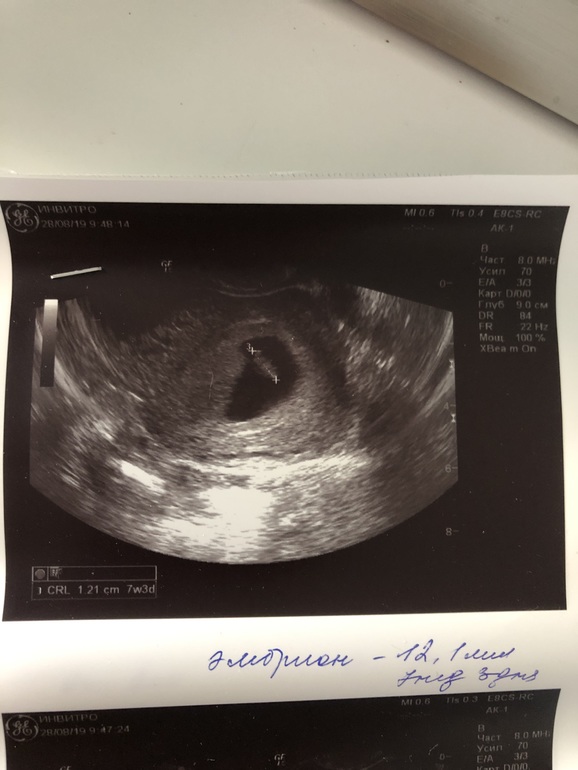

УЗИ и наконец сердечко🙏🏻 7нед 4дня

УЗИ, КТГ, доплерОх, какими же мучительными были 10 дней. Впервые пошла на УЗИ перед командировкой, срок был 6 нед 1день. Не увидели эмбриона и поставили совсем маленький срок. Тошнота ушла, грудь болеть перестала, никаких ощущений не было. Поэтому казалось, что что-то не так. Но сегодня я наконец услышала сердце малыша. Это непередаваемое ощущение, плакала минут 15 потом😅

Нашли рядом с жёлтым телом кисту, 1,5 недели назад ее не было, кто-то сталкивался с таким? Сама рассосётся?